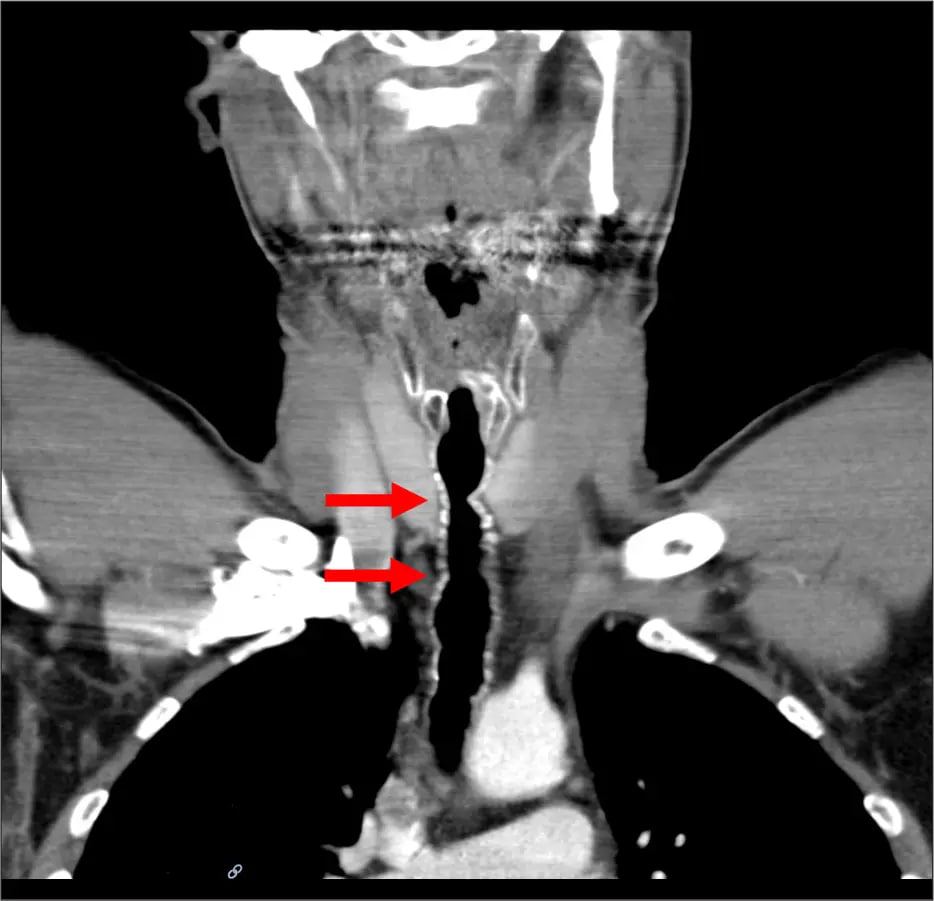

Впервые мужчина обратился к в больницу еще в 2007 году с жалобами на хриплый голос, постоянный кашель и затрудненное дыхание. Врачи обнаружили, что в его горле начали расти волосы там, где ранее была проведена операция по пересадке кожи. Предполагается, что именно сигаретный дым повлиял на рост волос в «неположенном месте».